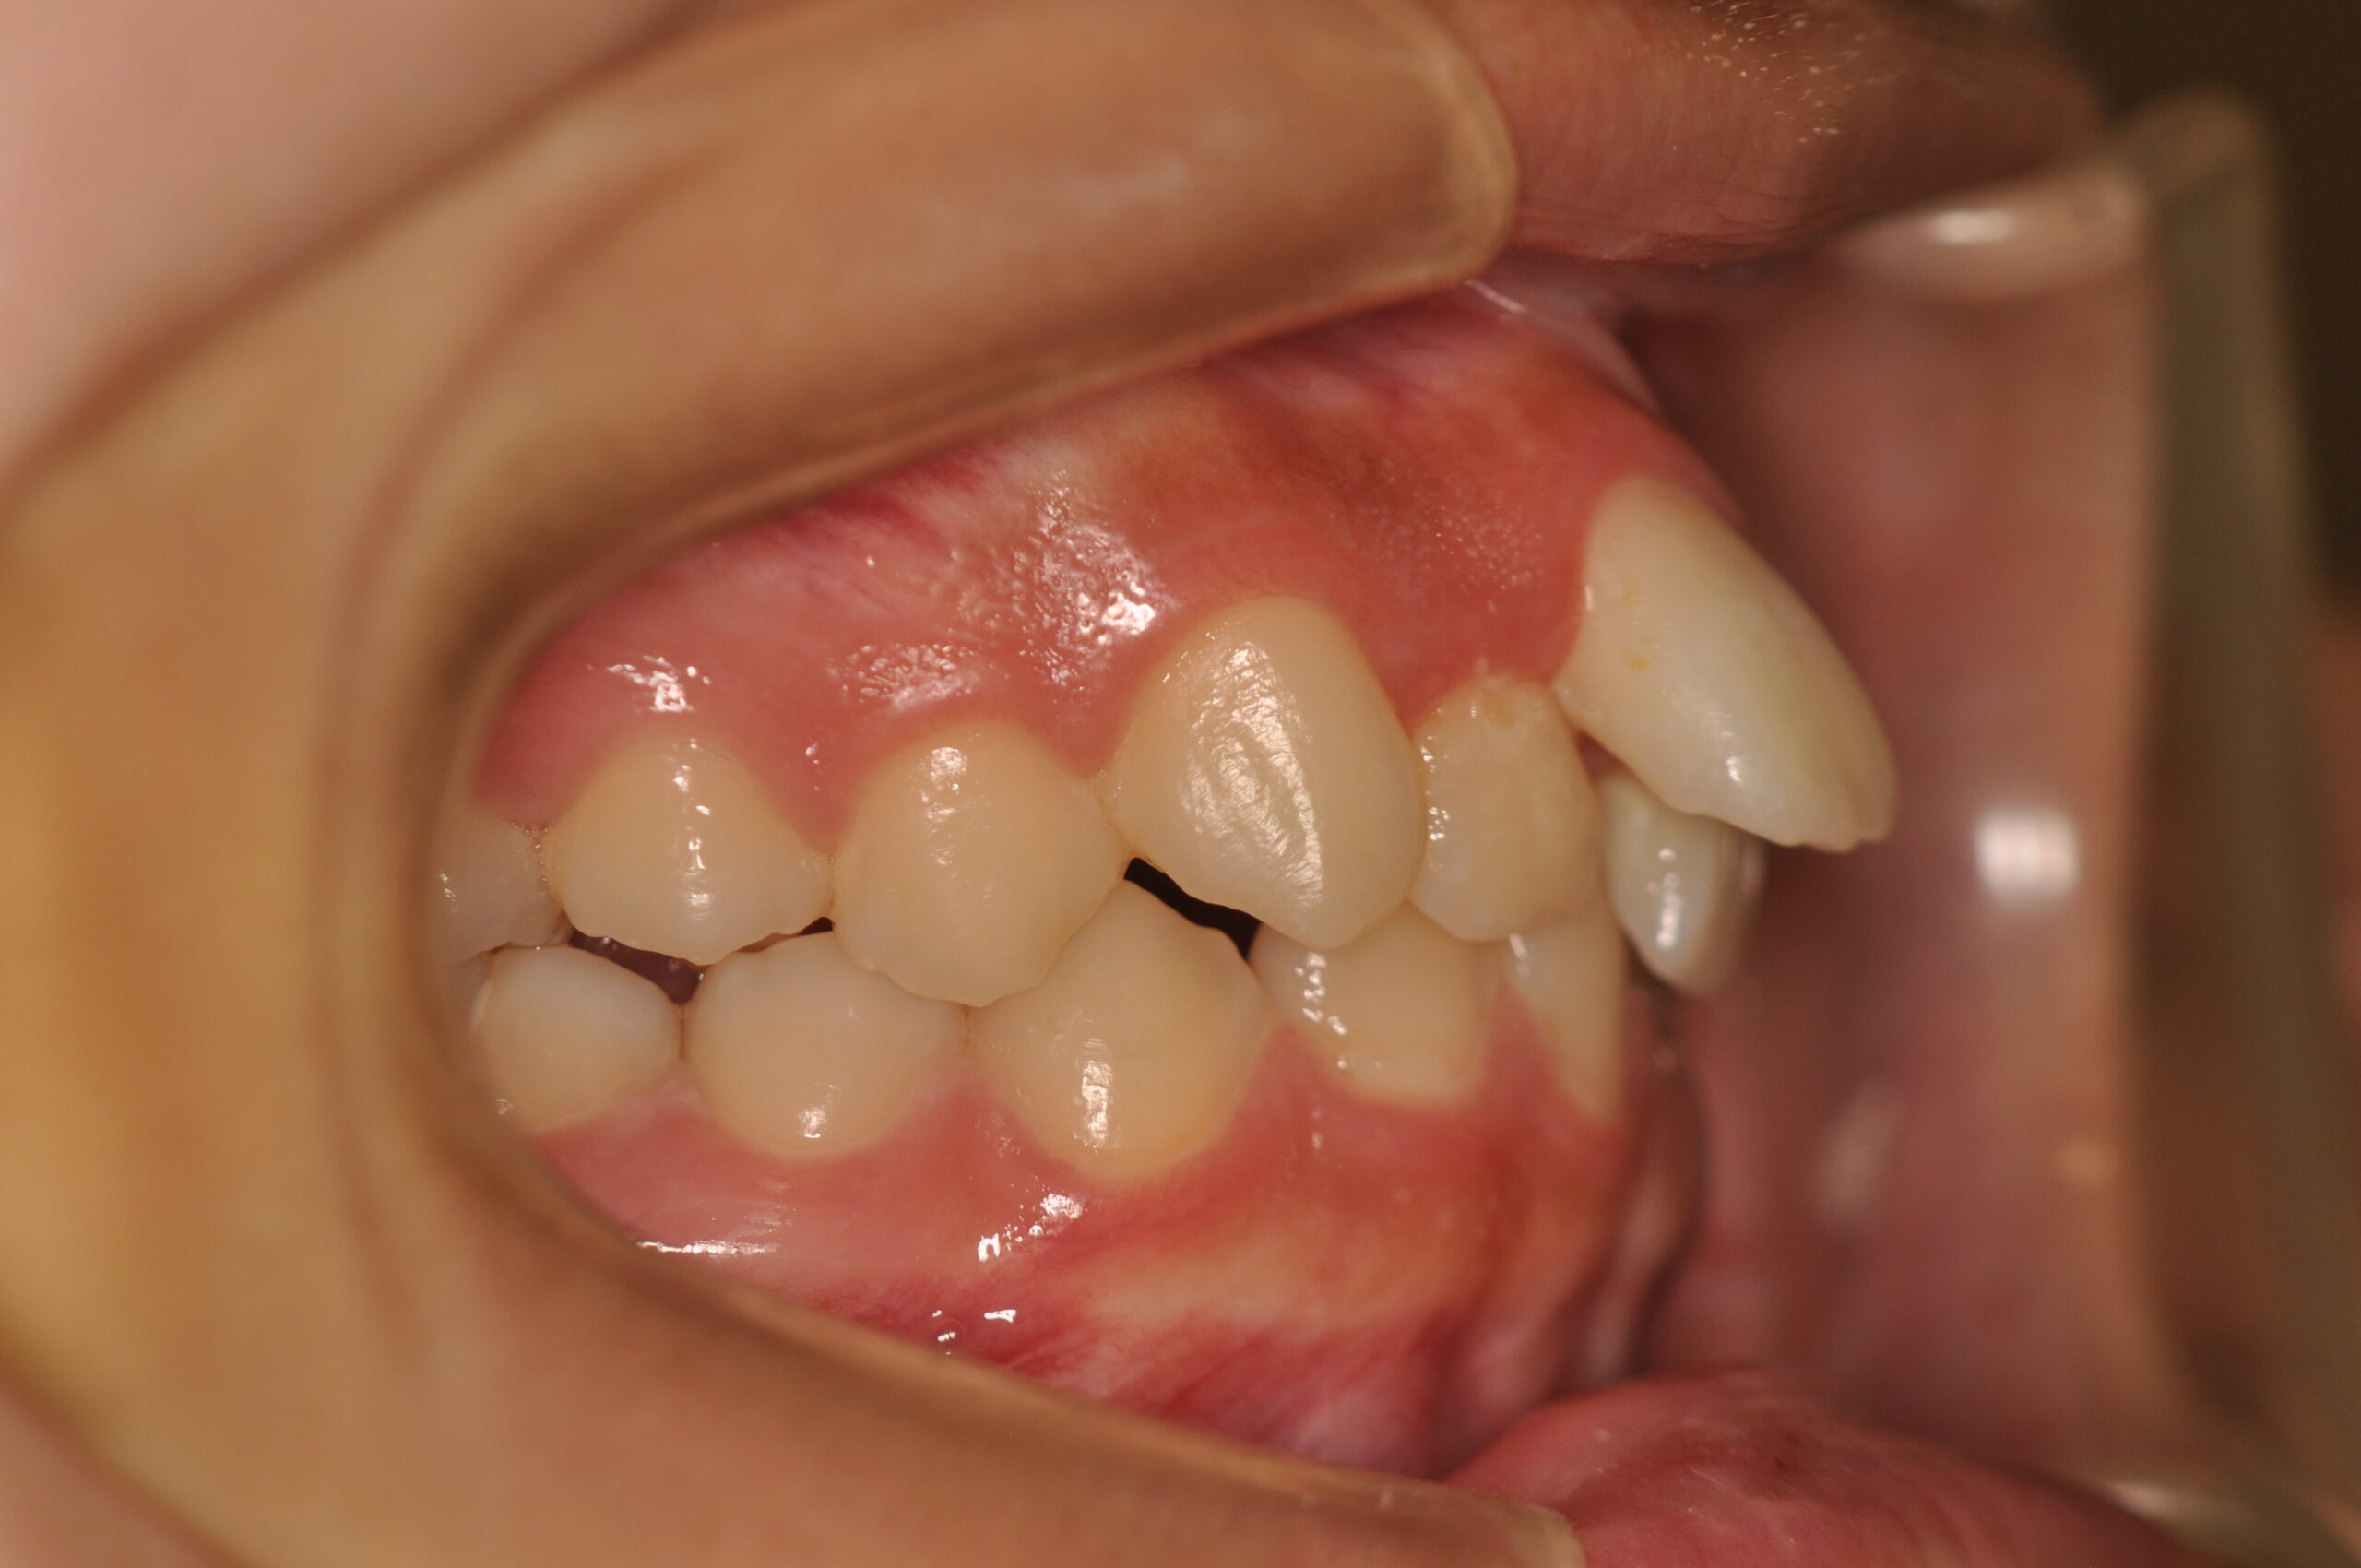

八重歯・でこぼこ(抜歯)【2142】

初診時

年齢

15歳 性 別 女性

治療内容の詳細 初診時15歳の女性で、歯のがたつきを気にされ来院されました。

検査の結果、上下顎前歯部叢生を伴うアングルⅠ級不正咬合と診断しました。

治療としては、上顎第一小臼歯を抜歯し、セルフライゲーションブラケット装置(デーモンシステム)とマウスピース型矯正装置(インビザライン)で配列を行いました。

同時に顎間ゴムにて咬合関係の改善を行いました。

この際、上顎に歯科矯正用アンカースクリューを設置し上顎前歯部後退時の土台としました。

治療期間は、2年3ヶ月でした。